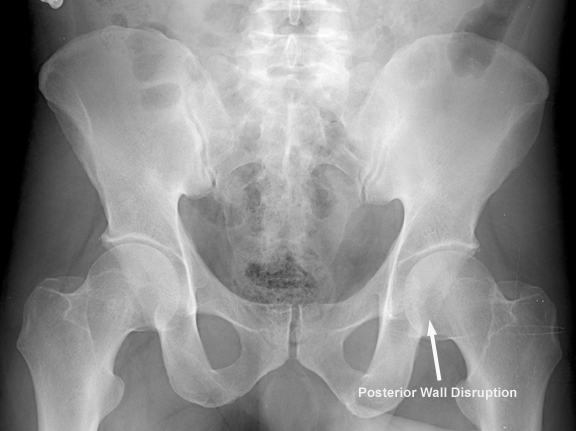

Posterior wall

x

• Most common

• "gull sign" on obturator oblique view

• Findings

• radiographic landmarks of the acetabulum

• anterior wall

• posterior wall

• gull sign

• represents impaction of superomedial roof

• seen on obturator oblique view

• pathognomic for posterior wall fractures